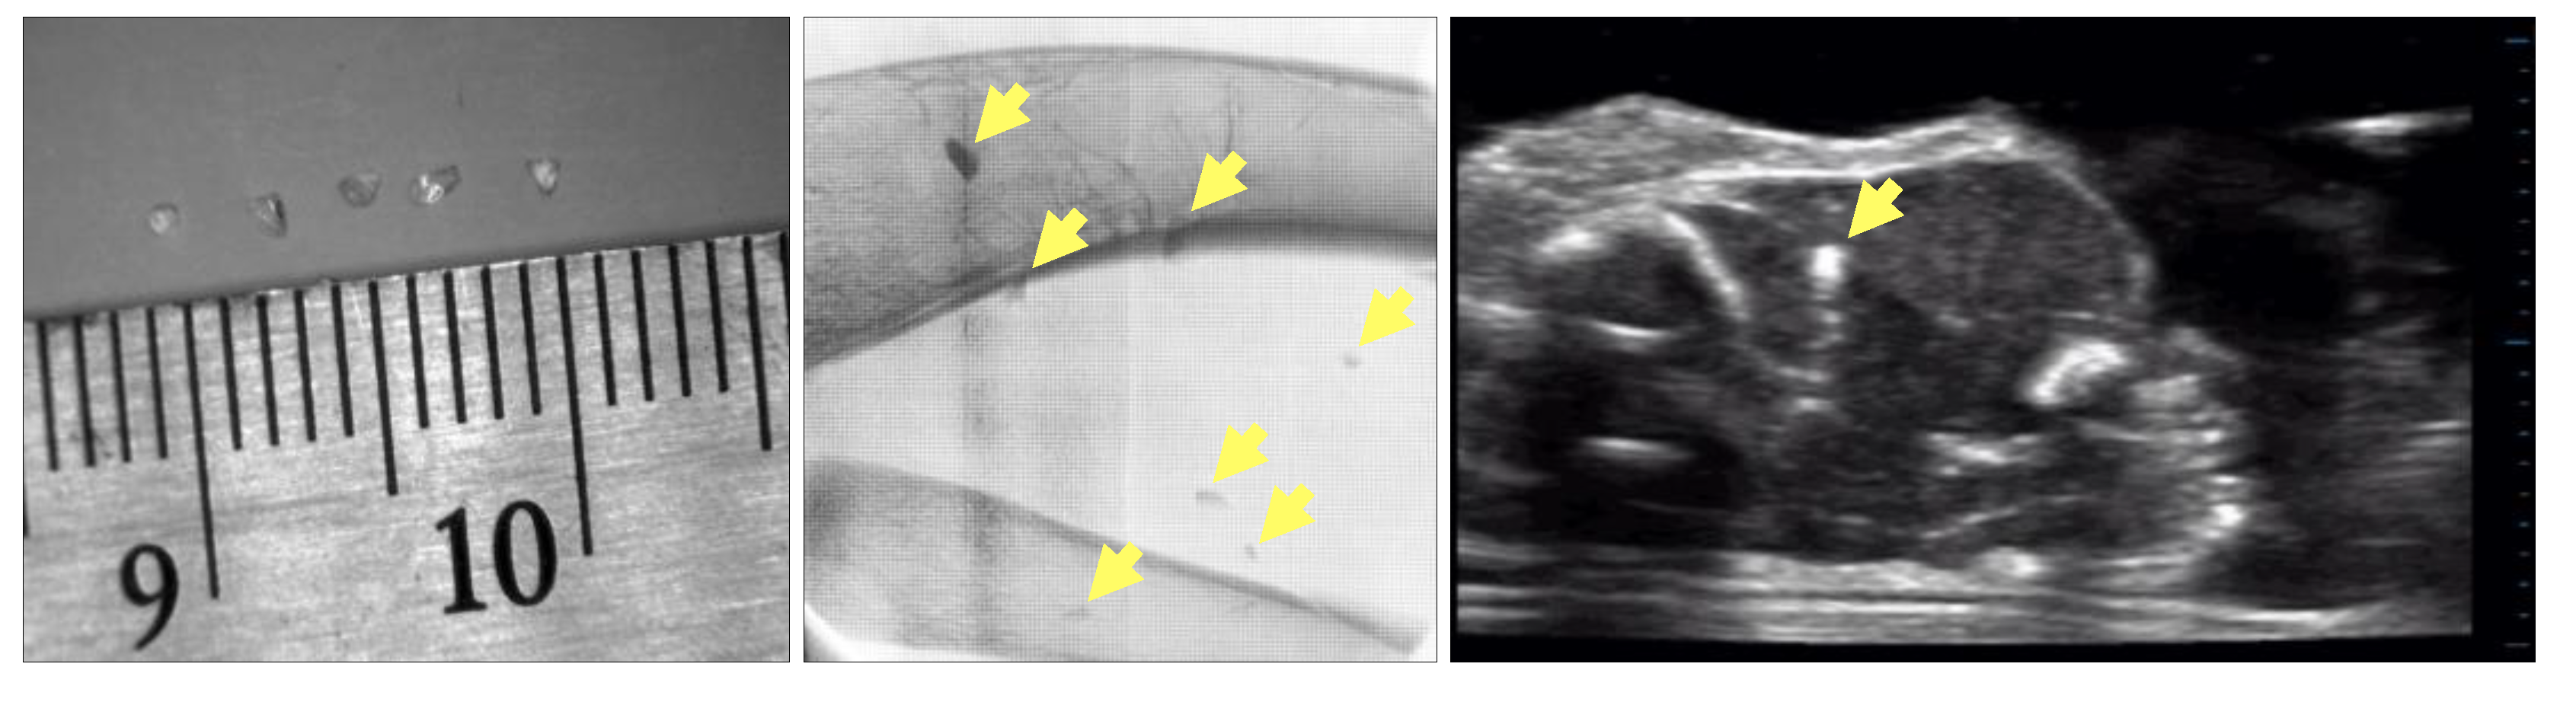

MFXI provides sufficient resolution for the detection of small glass fragments. It is particularly advantageous in comparison to ultrasound imaging. This is illustrated in Figure 1. These images were taken during the early phase of our study. Examples of glass fragments are shown. The MFXI image clearly shows seven glass fragments. The ultrasound image of the same sample only shows one fragment.

Figure 1.

(Left) Image of glass fragments as small as 1 mm; (Middle) X-ray image of sample with embedded glass fragments; Multiple fragments are visible (yellow arrows). (Right) Ultrasound image of same sample; one fragment is visible (yellow arrow). This image was taken with a linear-array (15–4 MHz) transducer using a uSmart® Terason 3200T US (Burlington, MA, USA).